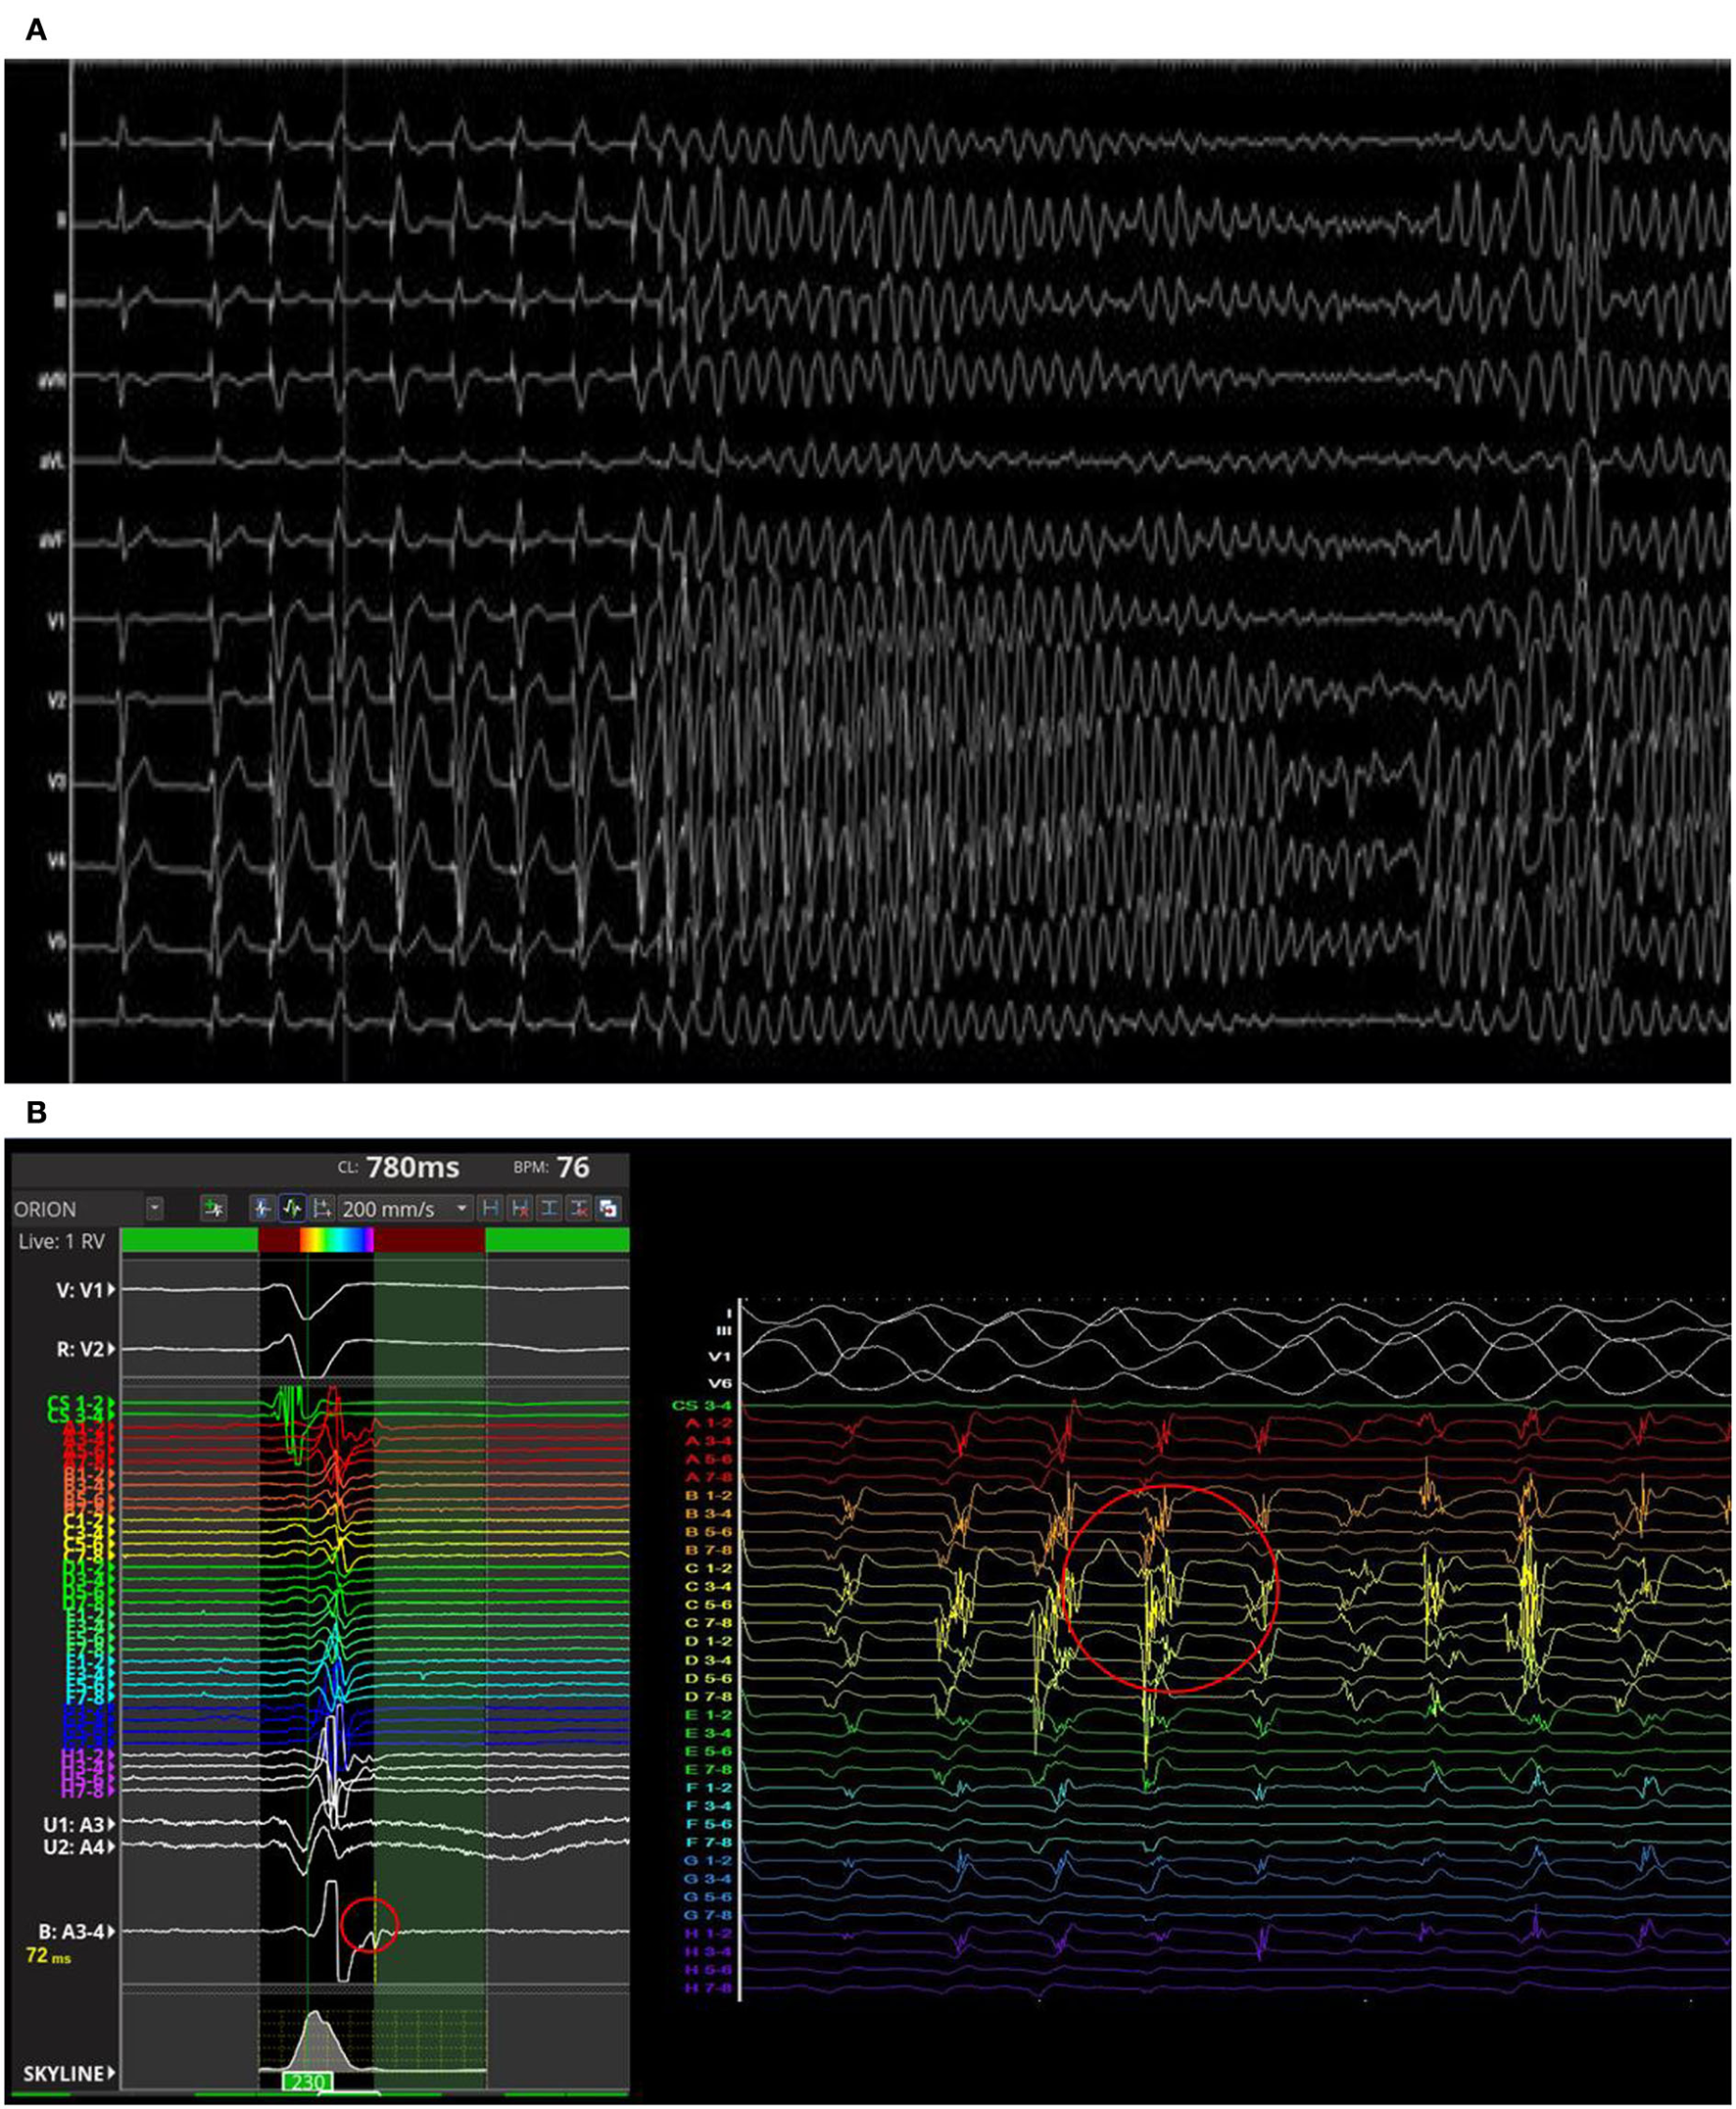

The PVS from RVOT with a paced drive train at cycle length of 500 ms followed by two extrastimulus at 220 and 200 ms respectively revealed the induction of a sustained polymorphic ventricular tachycardia (PVT) symptomatic for syncope and treated by external DC-shock (Figure 3A). During the arrhythmic event, the early diastolic potentials were recorded by the high-density diagnostic catheter (IntellaMap Orion™, Boston Scientific Corporation, US) placed in RVOT (Figure 3B). Subcutaneous ICD implantation was performed in order to prevent the sudden cardiac death. At 6 months follow-up, the patient did not experience arrhythmic events. The molecular genetic analysis showed a c.1718C>T heterozygous variation on exon 11 of Lamin A (p. Ser573Leu). Family members were genetically screened and the probands' sister and daughter showed the same LMNA mutation in absence of ECG abnormalities.

Figure 3

Polymorphic ventricular tachycardia induced by programmed ventricular stimulation from right ventricular outflow tract (RVOT) (A). The early diastolic potentials were recorded by the mapping catheter placed in RVOT (B).